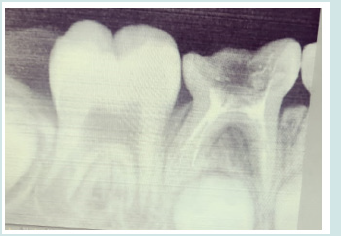

A girl child of 6 years had come to the department of pedodontic and preventive dentistry at the dental institution with a chief complaint of pain in the in the lower left back tooth region of jaw since past one week. On clinical examination she was having deep occlusal caries with respect to tooth number 85. Radiographically, the caries had progressed to the pulp chamber. The presence of third root/ additional root was also revealed. The diagnosis of chronic irreversible pulpitis with 85 was made (Figure 1). It was also found through radiograph that extra root was present with respect to 84 and 75 which were healthy. The tooth was isolated and access opening was done under local anesthetia and all the canals were located. Those were mesiobuccal, mesiolimgual, distobuccal and distolingual with the working length of 15mm in all the four canals (Figure 2). Cleaning and shaping of all the canals were done. Followed by obturation with metapex (Figure 3). The cavity was then sealed with permanent restorative material followed by stainless steel crown cementation.